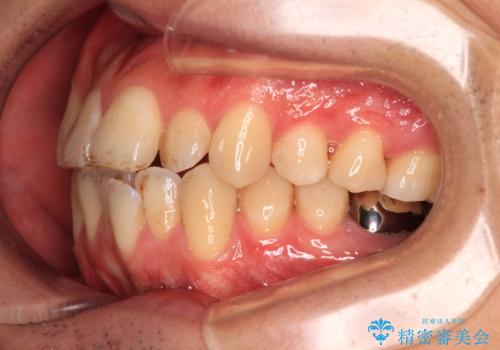

これらの問題を総合的に改善するため、上下左右の第一小臼歯を計4本抜歯し、スペースを確保する治療計画を立てました。

抜歯したスペースを活用して前歯を後ろへ下げることで、口元の突出感を大きく改善。

奥歯の噛み合わせがずれている「シザーズバイト」を適正に整えることで、見た目だけでなく機能性も向上し、安定した咬合が獲得できました。